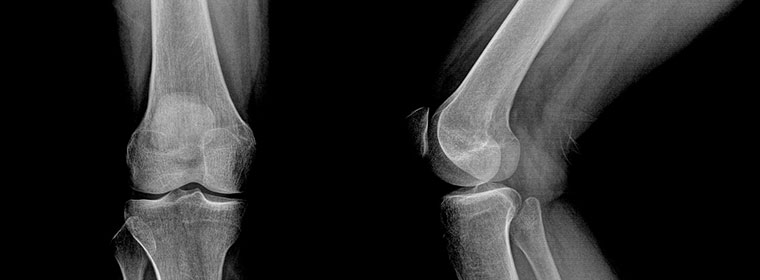

Knee Surgery

Types of knee surgery

As the population ages, more joint surgery is being performed to treat or replace worn-out arthritic joints. As concerns the knee, these operations include arthroscopy procedures and arthroplasty joint replacement procedures.